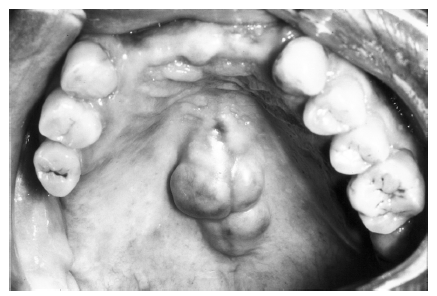

Figure 60 - Maxillary Torus

Figure 60

The maxillary torus presents as a hard, frequently lobulated, benign overgrowth of mature lamellar bone. It is frequently located in the midline of the hard palate (Figure 60) and attached by a broad, bony base.